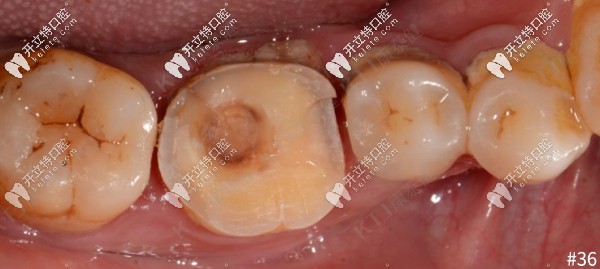

1、36牙體預(yù)備:全覆蓋式高嵌體洞型預(yù)備,IDS,近髓處采用樹(shù)脂墊底,優(yōu)化洞型,保證洞型邊緣的釉質(zhì)層連續(xù),為嵌體粘結(jié)提供良好的封閉區(qū)。

36牙體預(yù)備